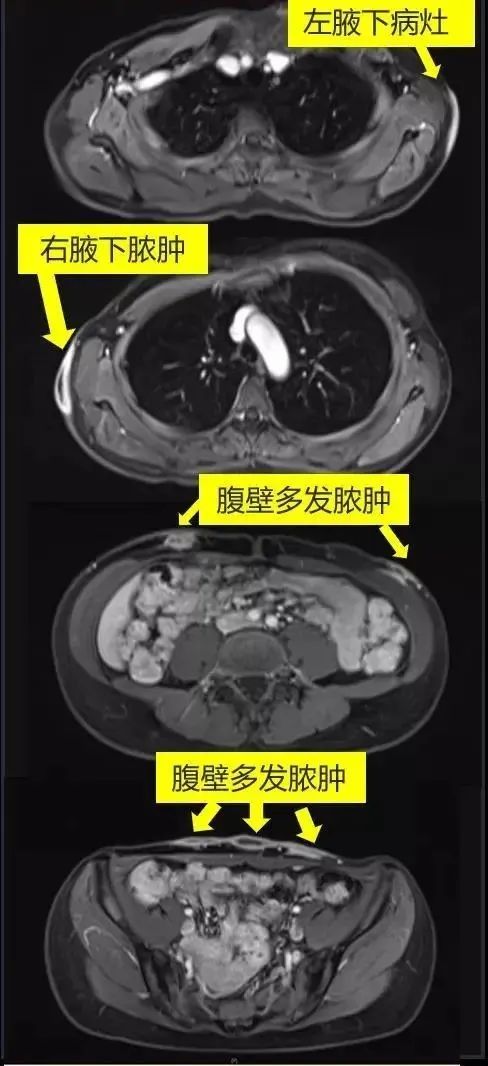

来到复旦大学附属中山医院感染病科门诊求助时,小美的情况已经更糟了:双侧腋下及腹部多发硬结较前进一步增大,脐周的病灶变成了一个鼓鼓的包块,右侧腋下和下腹壁的病灶也出现了溃破。“本来想追求美丽,没想到是这个结果。”小美既焦急又沮丧。为了进一步明确病因和诊疗,她被收治入中山医院感染病科病房。

入院后,医生赶紧为小美安排了相关检查,这一查,发现小美“埋蛋白线”处的皮下已有多处脓肿形成,其中最深之处已侵犯到了肌肉层。医生迅速为她抽取了一处病灶内的脓液送微生物检查,根据初步的培养结果,经验性使用了联合抗生素治疗。并为小美请来整形外科专家会诊,进行了多处脓肿的切开引流手术。经验丰富的手术医生非常乐意听取感染科医生的意见,术中仔细留取了各个部位的脓液和组织,进行的微生物学检查。